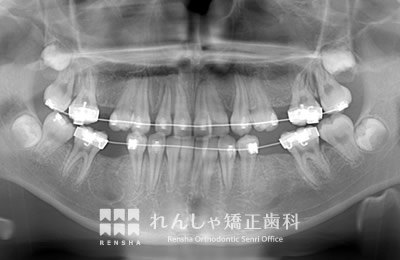

永久歯列はほぼ完成してしますが、歯列を側方だけでなく後方へも拡大し、埋まっていた右上奥歯を引っ張り出しています。

| 主訴 | 埋まったままでてこない歯がある |

|---|---|

| 診断名 | Angle Class II 小臼歯の埋伏と叢生を伴う上顎前突 |

| 初診時年齢 | 13歳5か月 |

| 装置名 | マルチブラケット装置 |

| 抜歯非抜歯 | 非抜歯 |

| 治療期間 | 2年3か月 |

| 費用の目安 | 約82万円+消費税(検査料金、都度の処置費用等も合わせた総額) |

| リスク副作用 | 歯の移動に伴う軽微な歯根吸収、歯槽骨吸収、歯肉退縮(本症例では軽度の歯根吸収を認めた)、矯正器具装着中のカリエスリスク増大(本症例ではカリエス発生無し) |